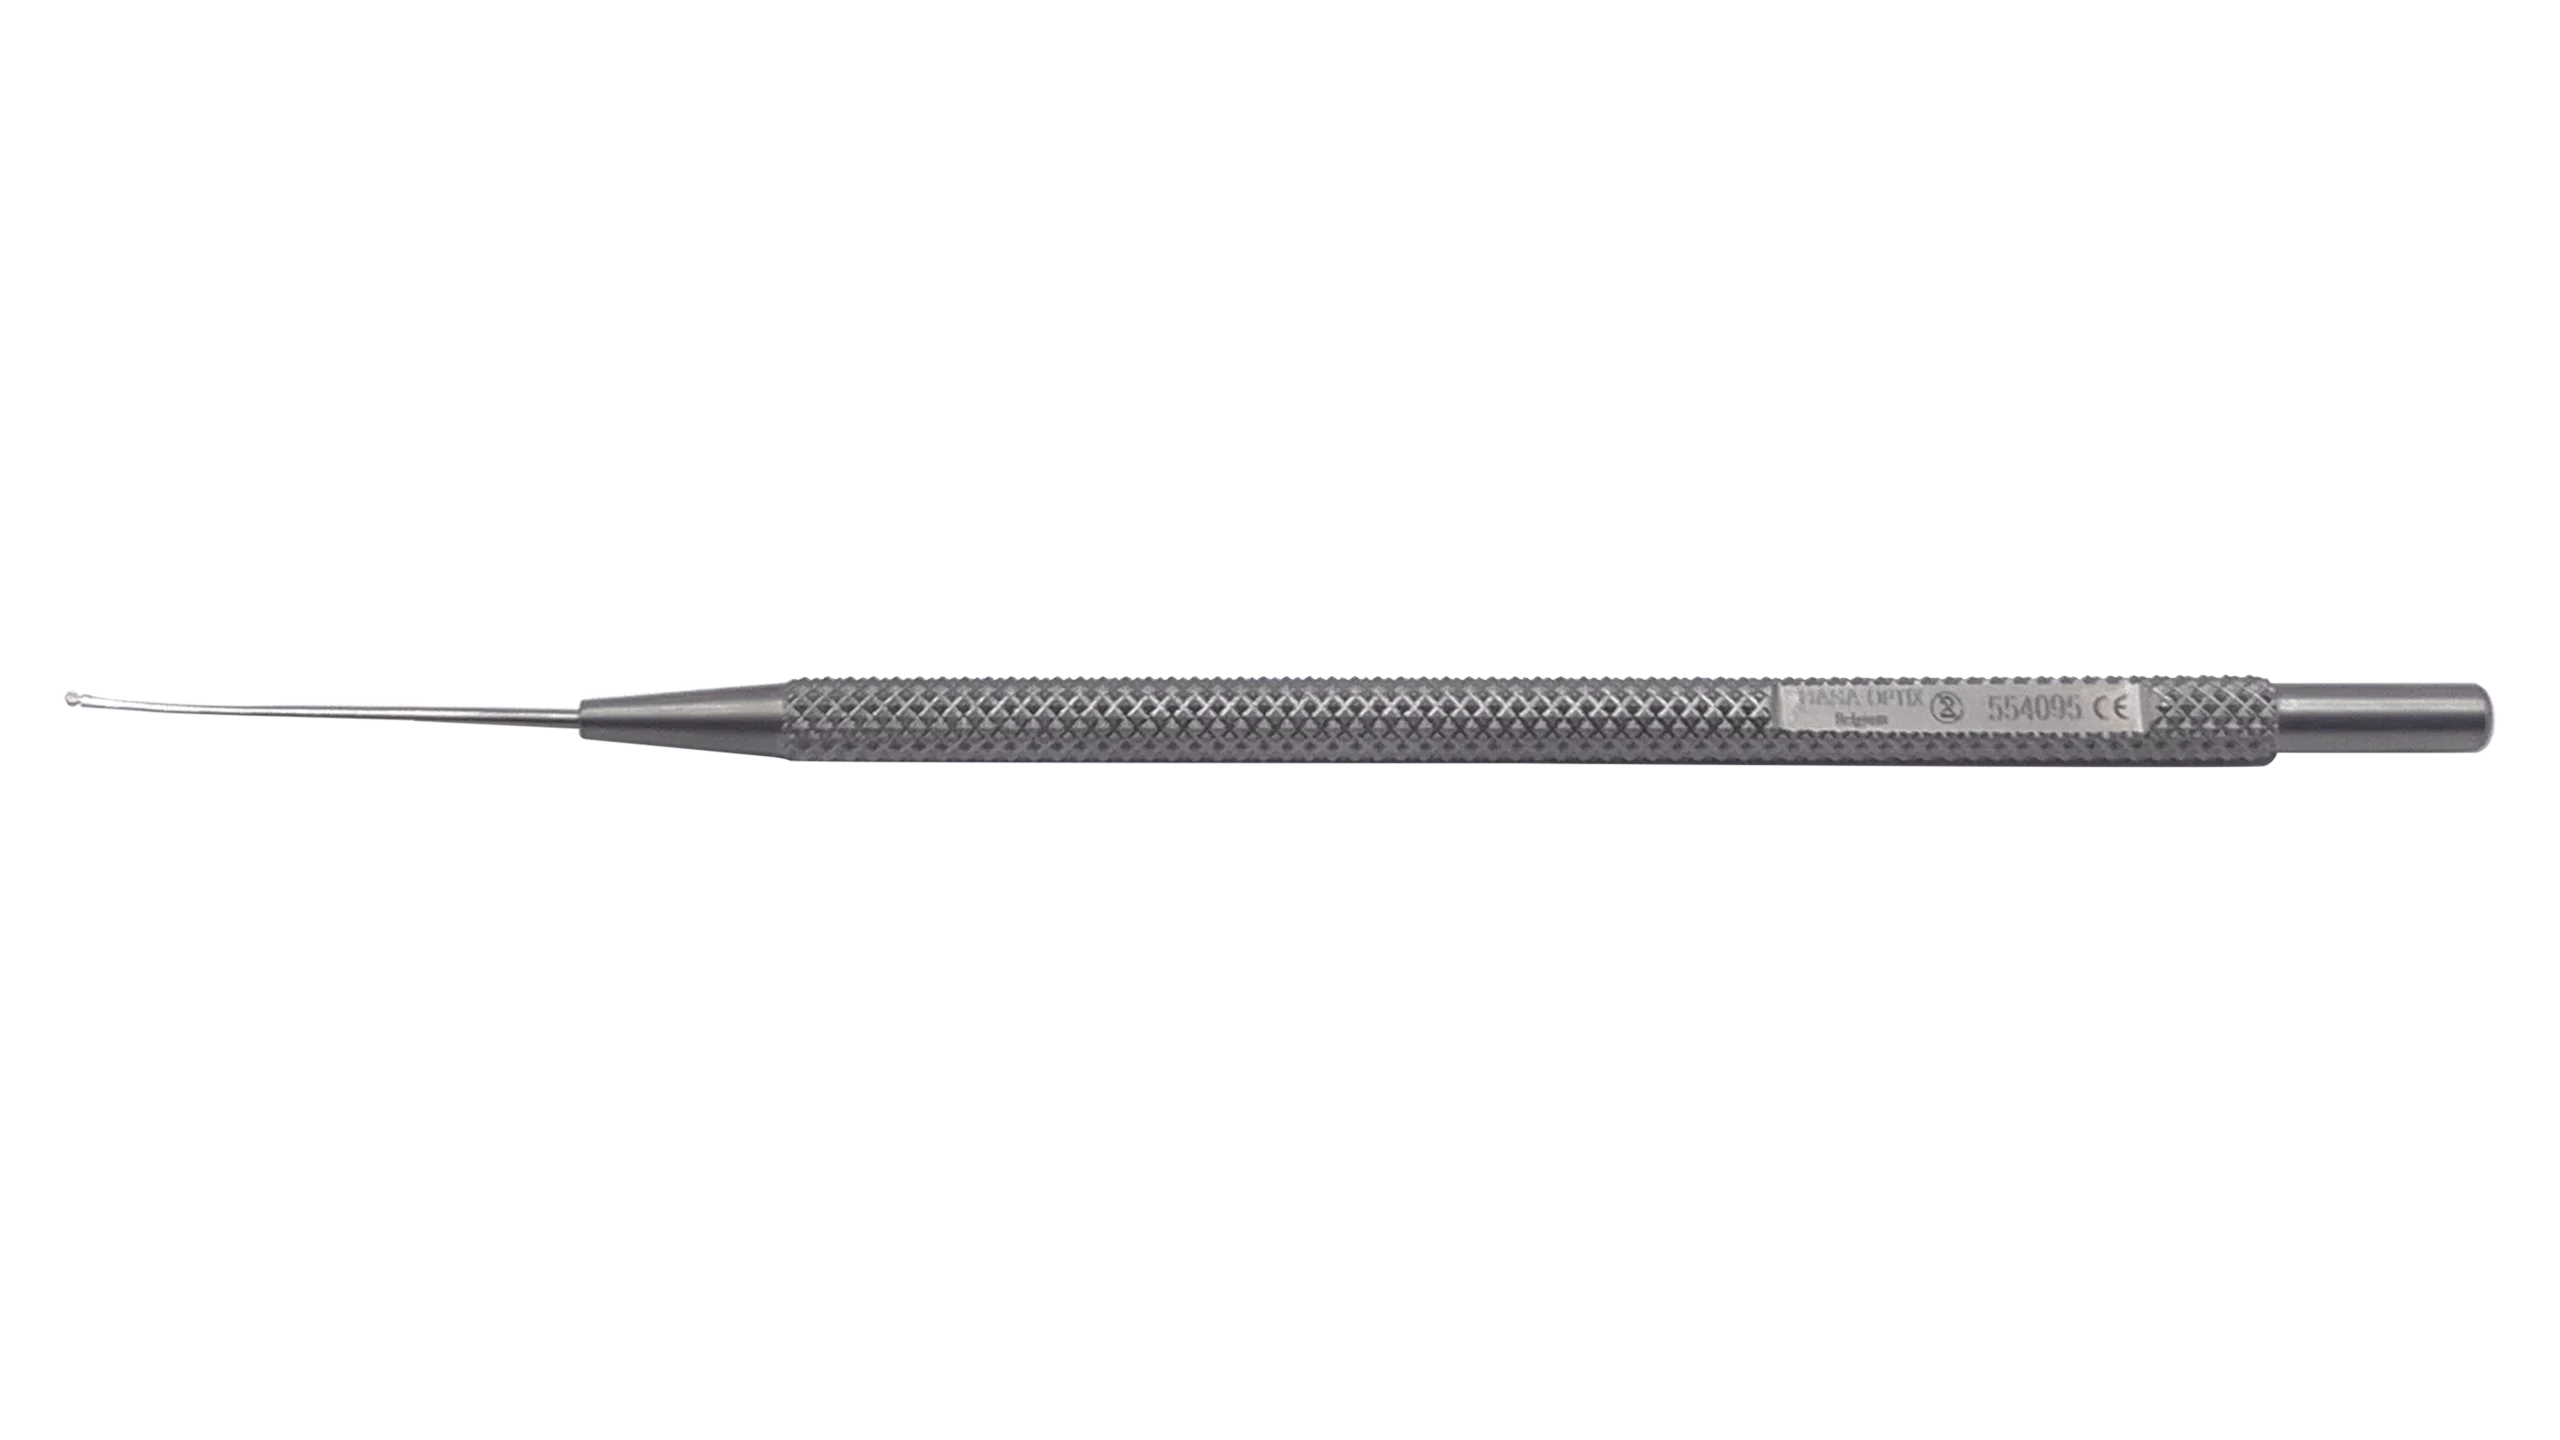

Ophthalmic Surgical Instruments

Wide range of recyclable ophthalmic surgery instruments.